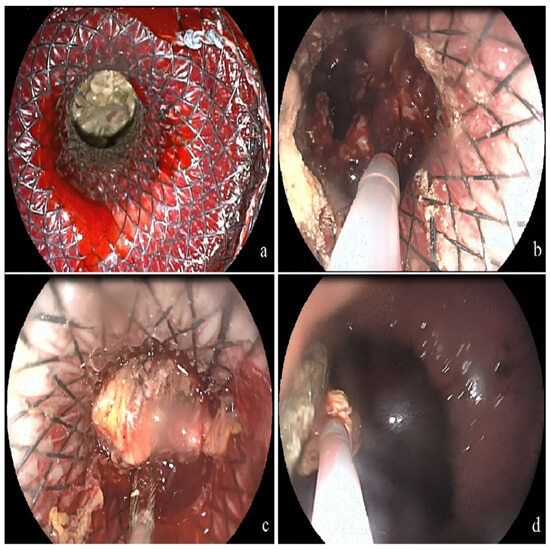

3.2. Initial Outcomes of Endoscopic Intervention

3.3. The Addition of Percutaneous Intervention as a Step-Up Approach

3.4. Outcomes of Complications, Recurrence, and Follow-Up